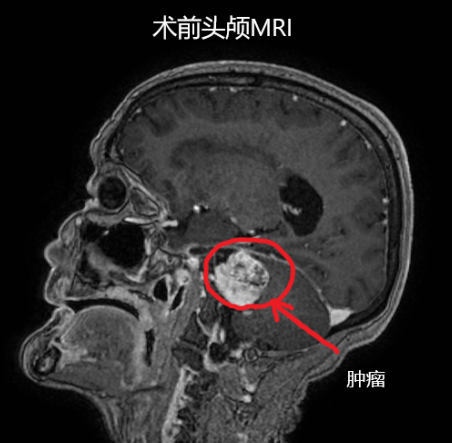

老阿妈入住医院神经外科后,主管医生对患者做了详细体格检查、头颅MRI检查明确原因,最终发现引起患者一系列症状的罪魁祸首是颅内长了一个“肿瘤”,结合患者症状初步诊断为“右侧桥小脑角占位:听神经瘤”,肿瘤已生长至3cm,在听神经瘤里已属于巨大肿瘤,并且已逐渐压迫脑干,如若不尽快手术切除,患者要面临的不仅仅是目前症状加重,更有可能引起生命危险。

面临两难的选择,家属们选择相信阿坝州人民医院神经外科的医生们,同意接受手术治疗,病人把自己的健康、甚至生命托付给了州人民医院的医生。2021年2月在华西医院神经外科的支持下,患者在全麻下行“经乙状窦后入路显微镜下听神经瘤切除术”,手术相当顺利,此刻家属焦急的心情才逐渐平复。术后患者的头颅MRI检查可见肿瘤已切除,病检结果为“听神经瘤”,符合医生们的判断。在阿坝州人民医院神经外科医护人员精心治疗和细致护理下,病人一步一步逐渐康复,家属脸上也露出了开心的笑容。